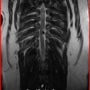

■ MRI検査

第5-6腰椎間で右側神経根が腫大し、脊柱管内に連続した腫瘤病変が認められました。脊髄および馬尾神経は右側から重度に圧迫されていました。

MRI検査所見

MRI 2